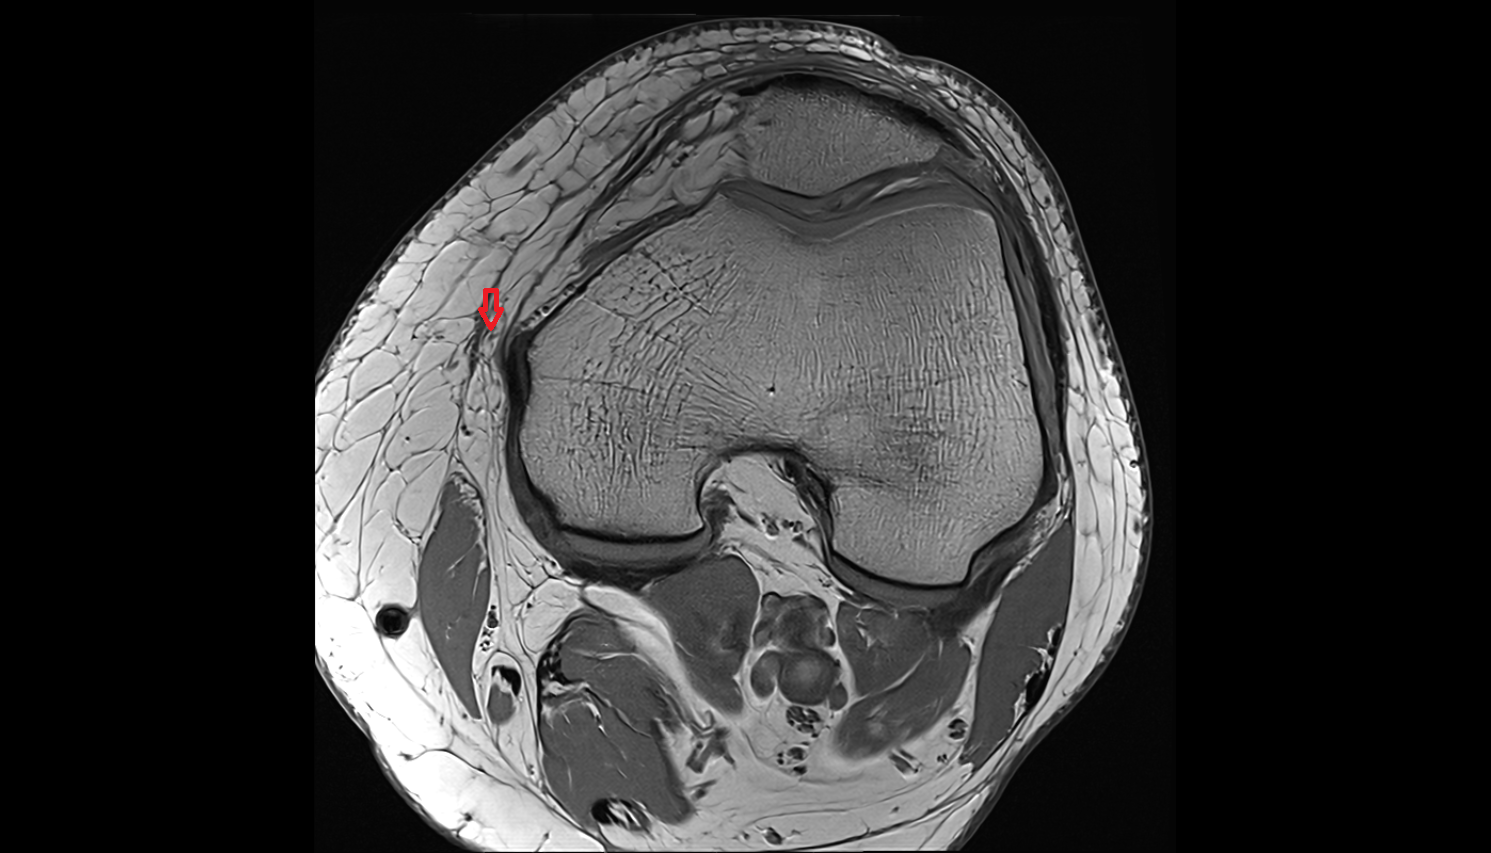

- Meniscus cartilage

- Medial meniscus

- Lateral meniscus

- Knee Joint